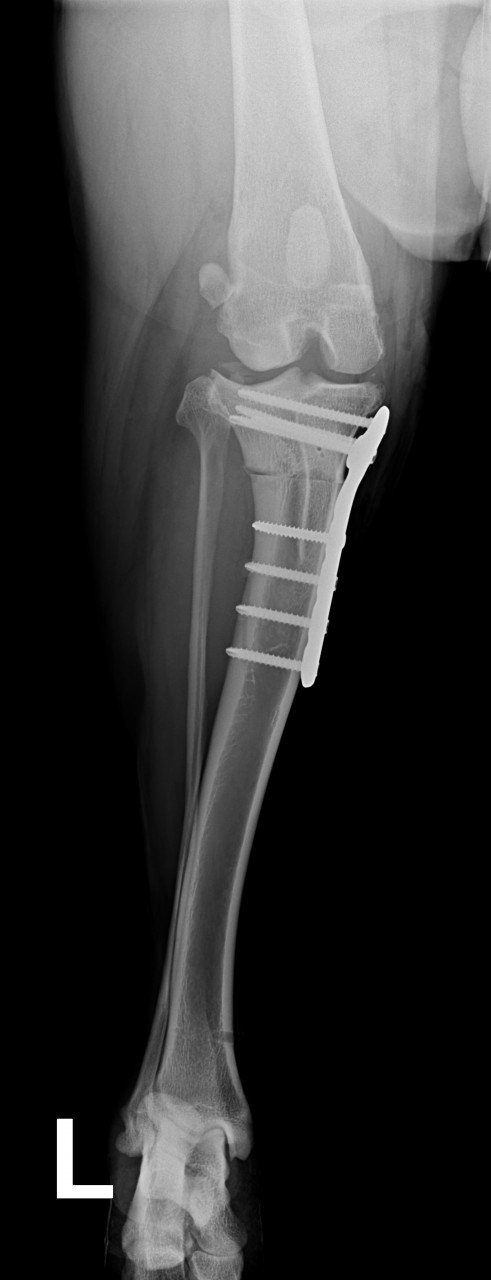

Falls es wenn interessiert das sind die Röntgenbilder von der OP.

Da oben wo man die kleine Ecke sieht, hat man den Schienbeinkopf zersägt und gedreht